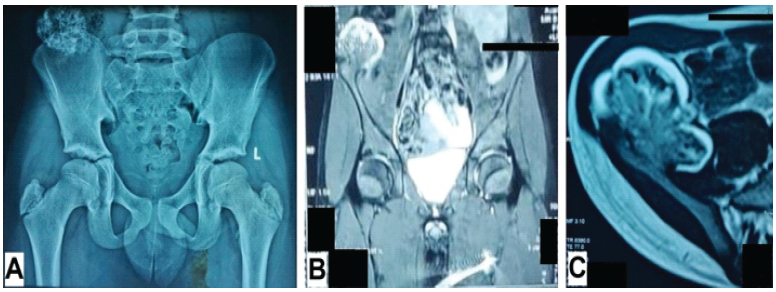

A preliminary pelvic radiograph revealed skeletal immaturity (Risser grade 0). The presence of a radio-opaque, popcorn-like mass arising from the inner table of the anterosuperior aspect of the right ilium was noted (Fig. 1). Magnetic resonance imaging (MRI) findings were pathognomonic for an osteochondroma, showing a well-defined pedunculated lesion arising from and continuous with the underlying ilium (Fig. 1).

Figure 1: Pre-operative radiologic investigations of the first patient. (a) Anteroposterior radiograph of the pelvis with both hips, (b) magnetic resonance imaging of pelvis (coronal section), and (c) magnetic resonance imaging of the right hemipelvis (transverse section). (Potential patient identifiers have been blacked out).

The thickness of the stalk of the lesion was noted to be approximately 2 cm. The mass was polypoidal in shape and measured 3.0 × 5.0 × 4.1 cm. An overlying cartilaginous cap measuring a maximum of 7 mm in thickness was noted. The lesion was found to be abutting the anterolateral abdominal wall and was in close proximity with the lateral aspect of the right psoas major muscle and the ascending colon. Superiorly, it extended up to the level of the inferior endplate of the L4 vertebra. No surrounding edema was noted, nor were signs of compression of the surrounding viscera or neurovascular structures. No pelvic lymphadenopathy was noted.